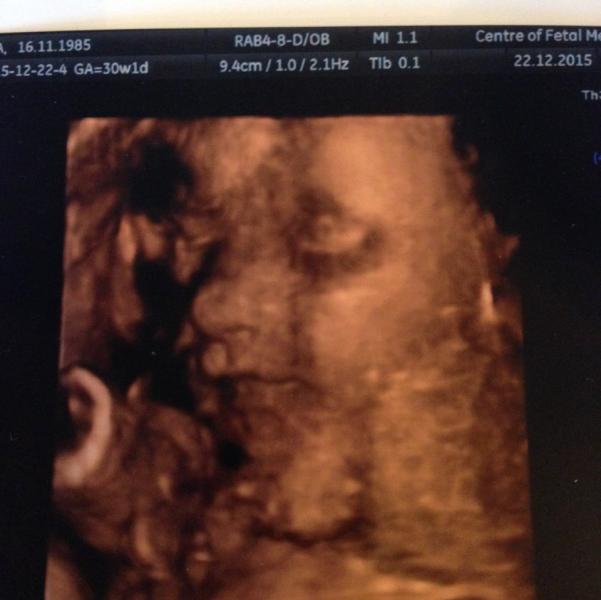

Ездили в Питер к друзьям, у меня как раз 30 недель было. Посоветовали нам 3д УЗИ в Центре медицины плода. Нам очень понравилось: все подробно рассказали, показали, фоток много дали и диск. А ещё открытку на память))) Вот эту фотографию мы выбрали на открытку. Наш скромняга постоянно прятался, еле поймали.